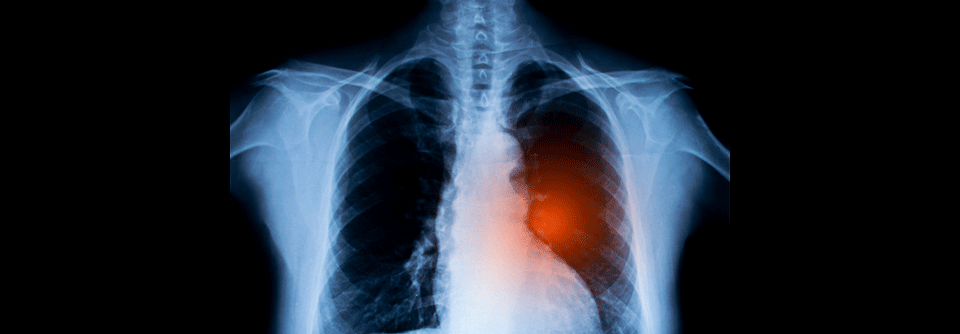

Wenn Palliation Vorfahrt hat: Stents können zu mehr Luft verhelfen. Wenn Palliation Vorfahrt hat: Stents können zu mehr Luft verhelfen. © Case courtesy of Dr Henry Knipe, Radiopaedia.org, rID: 31410